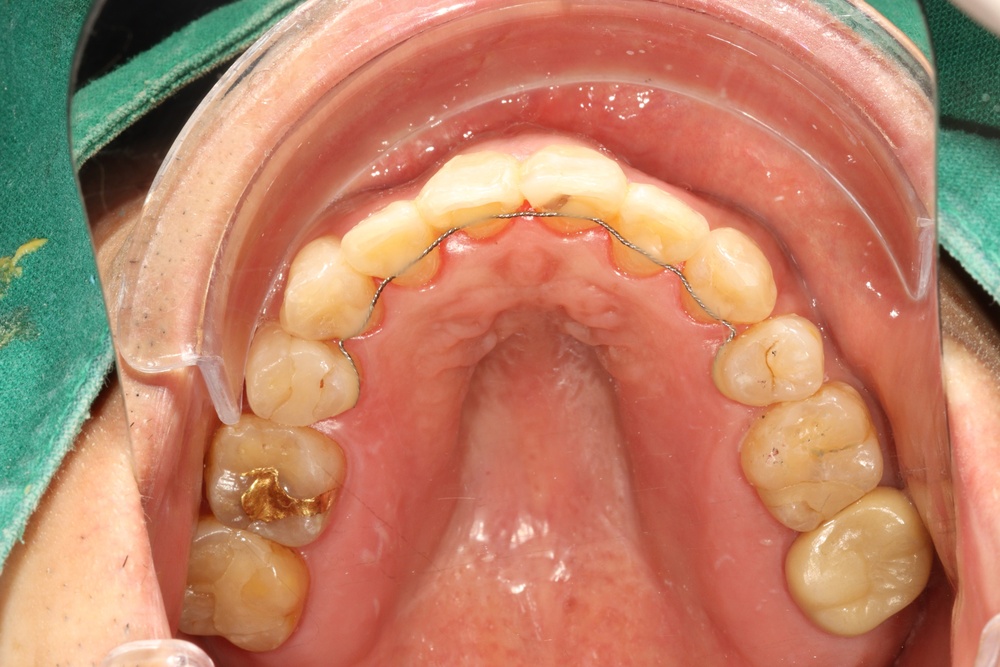

입천장의 고정식 확장장치를 이용해 좌우로 벌려서 치아를 배열할 공간을 만들었습니다.

전체 재제작을 위해 기존 유지장치를 제거한 상태입니다.

새로운 교정유지장치 철사도 부착해 드렸습니다.